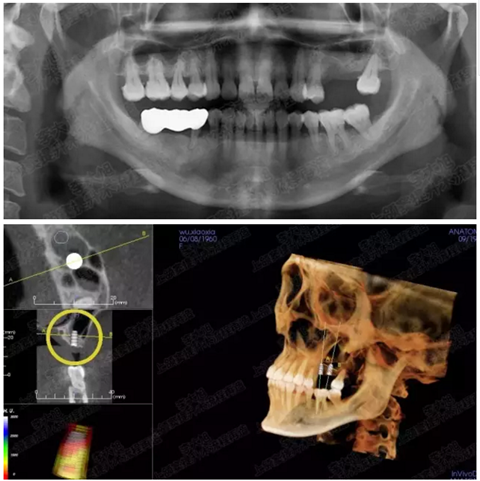

病例五

剩余不足1mm

112.png

提升10mm

113.png